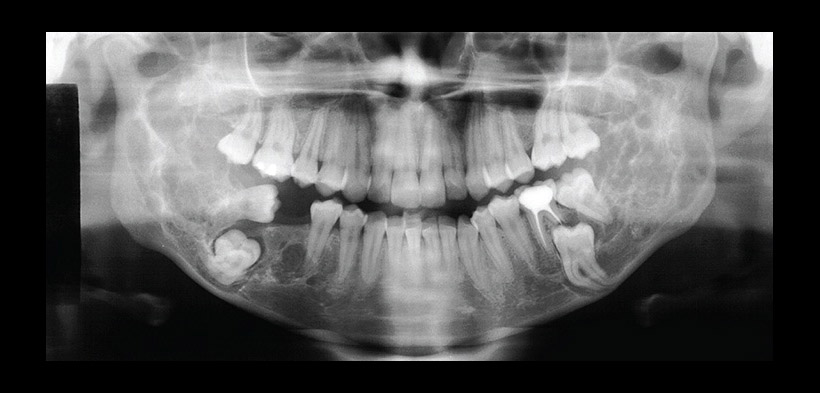

Fig. 3 Radiografía panorámica del paciente anterior posterior a la cirugía y a la administración de calcitonina, se observa la formación y la sustitución de la lesión por tejido óseo neoformado.